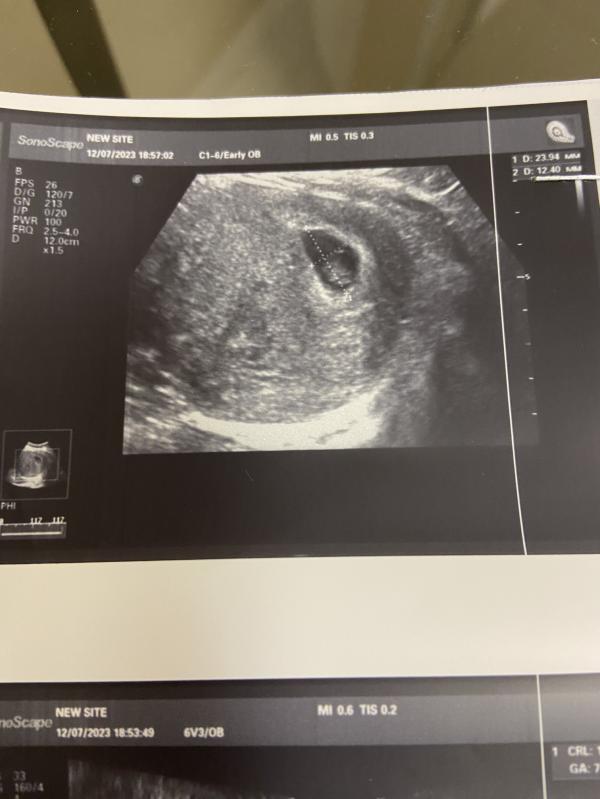

Что-то за эти два дня столько событий, что голова кругом! Вчера было первое узи нашей вишенки. А сегодня целый день приготовления к приходу гостей по поводу празднования др мужа.

И Мы сегодня были на узи тоже нашей вишенки )))